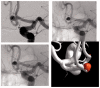

Introduction: The Neuroform Atlas Stent System is a recently introduced modification of the original Neuroform Stent System consisting of a hybrid design with open and closed cells. Initial experience, technical considerations and treatment outcomes including 1-year follow-up using the Atlas stent in combination with coil embolization are reported.

Discussion: In 29 cases, the stents were delivered and positioned without difficulty in deployment. Technical complications occurred in one patient related to advancement of the stent during delivery. One procedure-related clinical complication occurred with no permanent neurological deficit. On immediate post-treatment angiography, 29 of 30 aneurysms showed Raymond Class I or Class II occlusion. At 1-year follow-up, all 30 patients were clinically stable and 18 of 30 aneurysms showed Raymond Class I complete occlusion. Retreatment was performed in two patients with residual aneurysm.

Conclusions: The Atlas stent is technically safe and simple to implant and has a low thrombogenic potential. We experienced fewer problems associated with deployment and implantation, thromboembolic complications and hemorrhagic events compared with other types of stents, including braided stents. However, because of its low thrombogenic potential, partially occluded aneurysms or those with aneurysm remnants do not progress to complete occlusion.